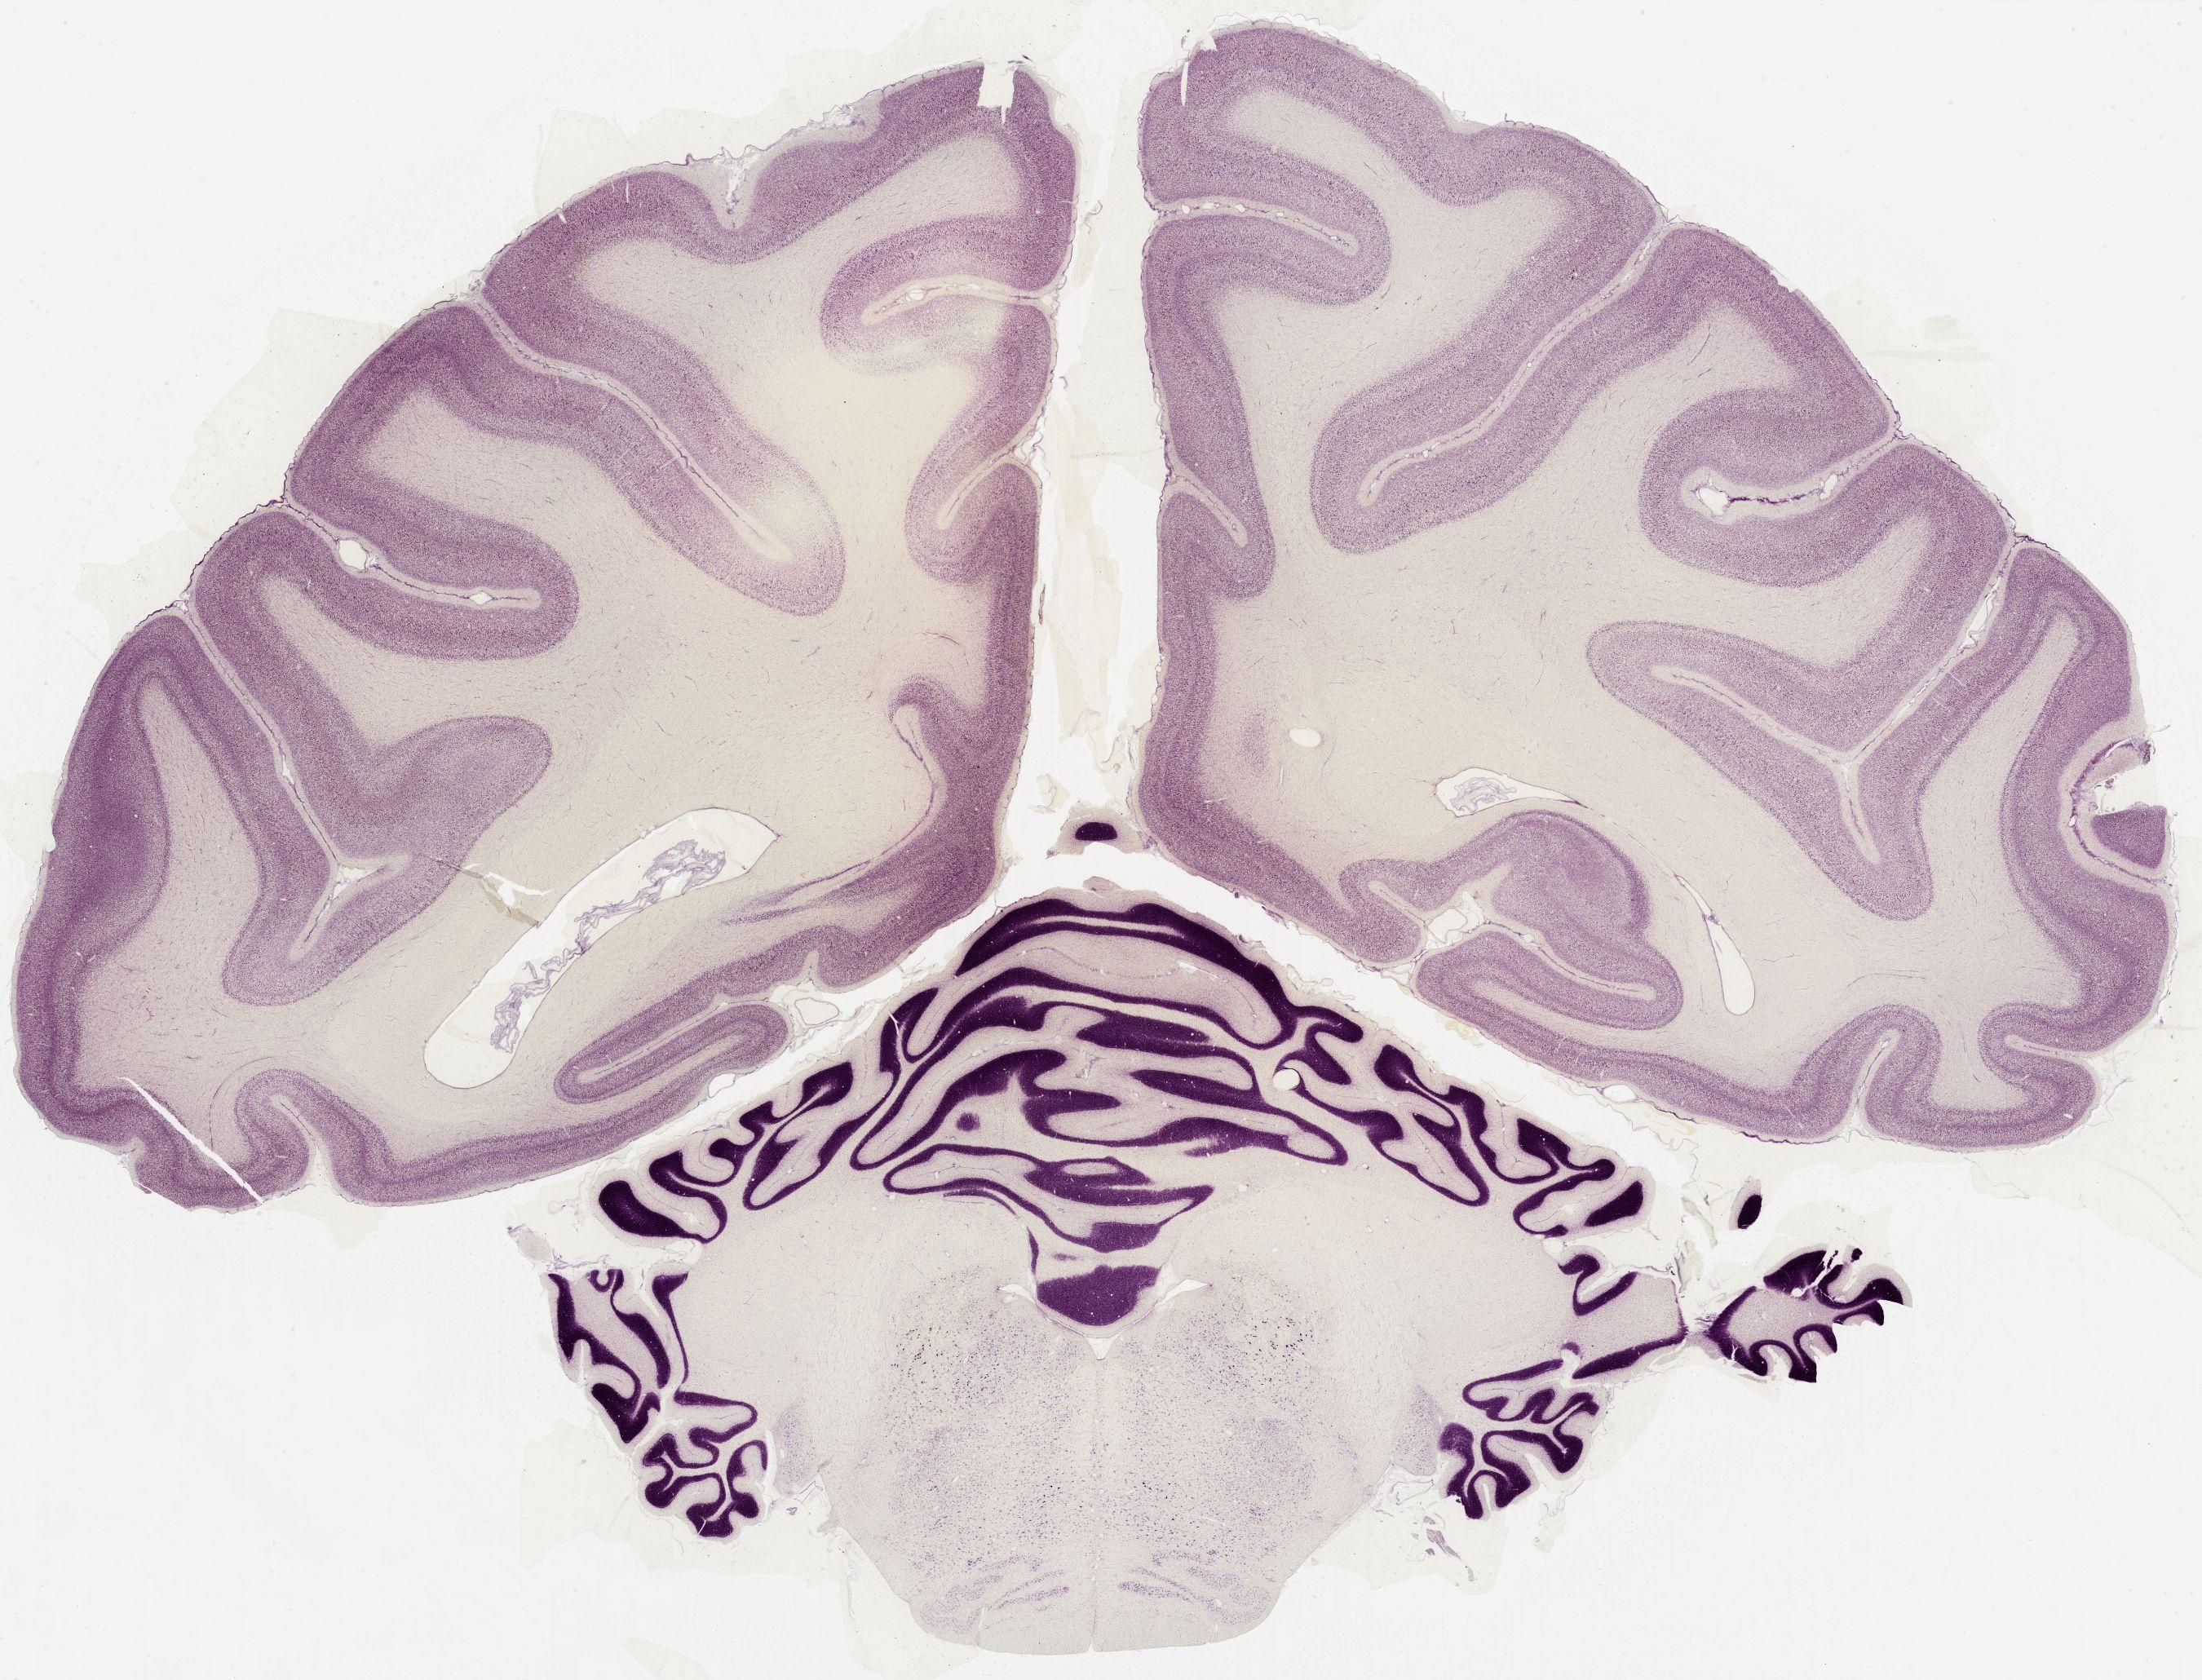

Datasets -> Macaca Mulatta -> Nissl, coronal, histo, Whole-Brain, adult

[ Metadata ]   ·   Source: Edward G. Jones

thumbnail

0601 - labeled